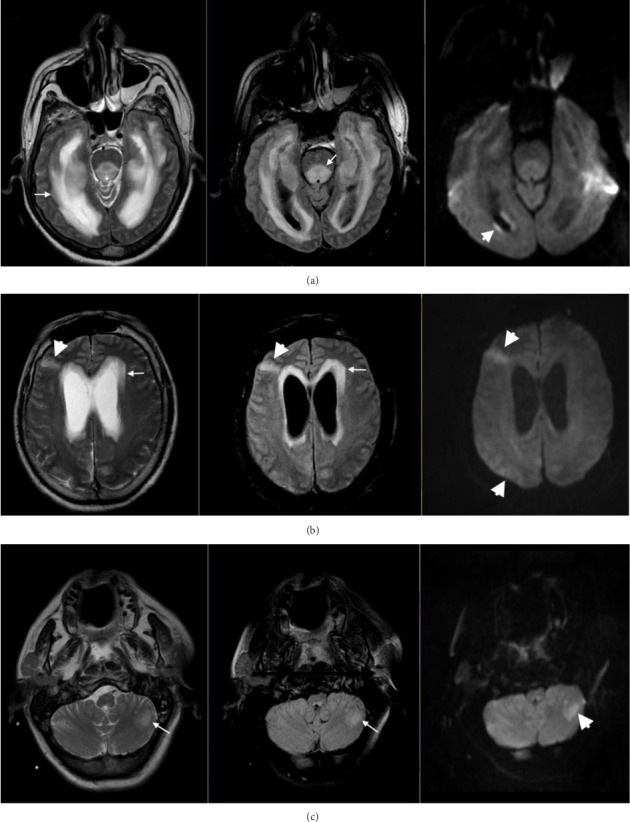

神经李斯特菌病是一种以累及脑实质和脑膜为特征的侵袭性李斯特菌病,病死率高,神经系统后遗症多。神经李斯特菌病的主要临床表现为脑膜炎、脑膜脑炎、菱形脑炎和脑脓肿。神经放射学成像有助于区分这些临床表现。神经李斯特菌病的诊断可通过脑脊液或血液培养来证实,但这些检查的结果可能因神经李斯特菌病的临床表现而异。老年人和免疫功能低下患者是发生神经李斯特菌病的最易感人群,在健康的年轻人中很少发生病例。这种疾病是由单核细胞增生李斯特菌引起的,这是一种具有细胞内生命周期的食源性病原体,可在加工食品中发现,它仍然是成人细菌性脑膜炎的第三个原因。大多数神经李斯特菌病病例是社区获得性的,但文献中也报道了一些医院获得性病例和疫情,这些病例和疫情与住院病人食用的食物有关。氨霉素是对神经李斯特菌病预后影响最大的抗生素,在无法使用首选抗生素或抗生素治疗失败的情况下,必须考虑其他抗生素治疗。本文综述了神经李斯特菌病的流行病学、感染源、发病机制和临床方面的研究进展,重点介绍了该疾病的主要临床表现。关于医院获得性神经李斯特菌病的相关信息也包括在内,以提供讨论医院病例定义的框架。

Neurolisteriosis is a listerial invasive disease, which is characterized by brain parenchymal and meningeal involvement, with a high fatality rate and frequent neurological sequelae. The main clinical presentations of neurolisteriosis are meningitis, meningoencephalitis, rhombencephalitis, and brain abscess. Neuroradiological imaging is useful to distinguish these clinical presentations. The diagnosis of neurolisteriosis may be confirmed by cerebrospinal fluid or blood cultures, but these tests may have different yields depending on the clinical presentation of neurolisteriosis. The elderly and immunocompromised patients are the most susceptible population to developing neurolisteriosis, and few cases occur in healthy young people. This disease is caused by Listeria monocytogenes, a foodborne pathogen with an intracellular life cycle, which can be found in processed foods, and it remains the third cause of bacterial meningitis in adults. Most cases of neurolisteriosis are community-acquired, but several hospital-acquired cases and outbreaks have been reported in the literature and linked to the consumption of food served to inpatients. Aminopenicillins are the antibiotics with the highest impact on the prognosis of neurolisteriosis, and alternative antimicrobial therapies must be considered in those cases where a first-choice antibiotic cannot be administered or with antibiotic treatment failure. In this article, the epidemiology, sources of infection, pathogenesis, and clinical aspects of neurolisteriosis are reviewed, highlighting the main clinical presentations of the disease. Relevant information regarding hospital-acquired neurolisteriosis is also included to provide a framework for discussing nosocomial cases definition.